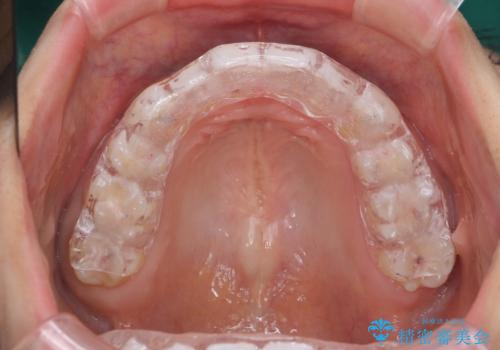

奥歯が欠けた セラミックインレーでの修復後、ナイトガード装着

欠けた部分にはセラミックインレーで修復処置を行い、今後の破折リスクを抑えるためにナイトガードを製作していきます。

食いしばりが強い方はセラミックがまた割れる可能性があるため、予防的にナイトガードを装着することをお勧めします。